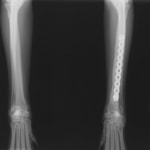

症例3:キルシュナーワイヤーのピンニングによる整復

ペルシャ猫 11ヶ月齢 雄

他院にて左大腿骨遠位の成長板骨折(salter-harrisⅠ型)が認められており、治療相談を目的として来院。当院にて、キルシュナーワイヤーを用いたピンニングにより骨折部位の整復を行いました。術後の経過は良好で、現在も経過観察中です。

術前レントゲン

術後レントゲン